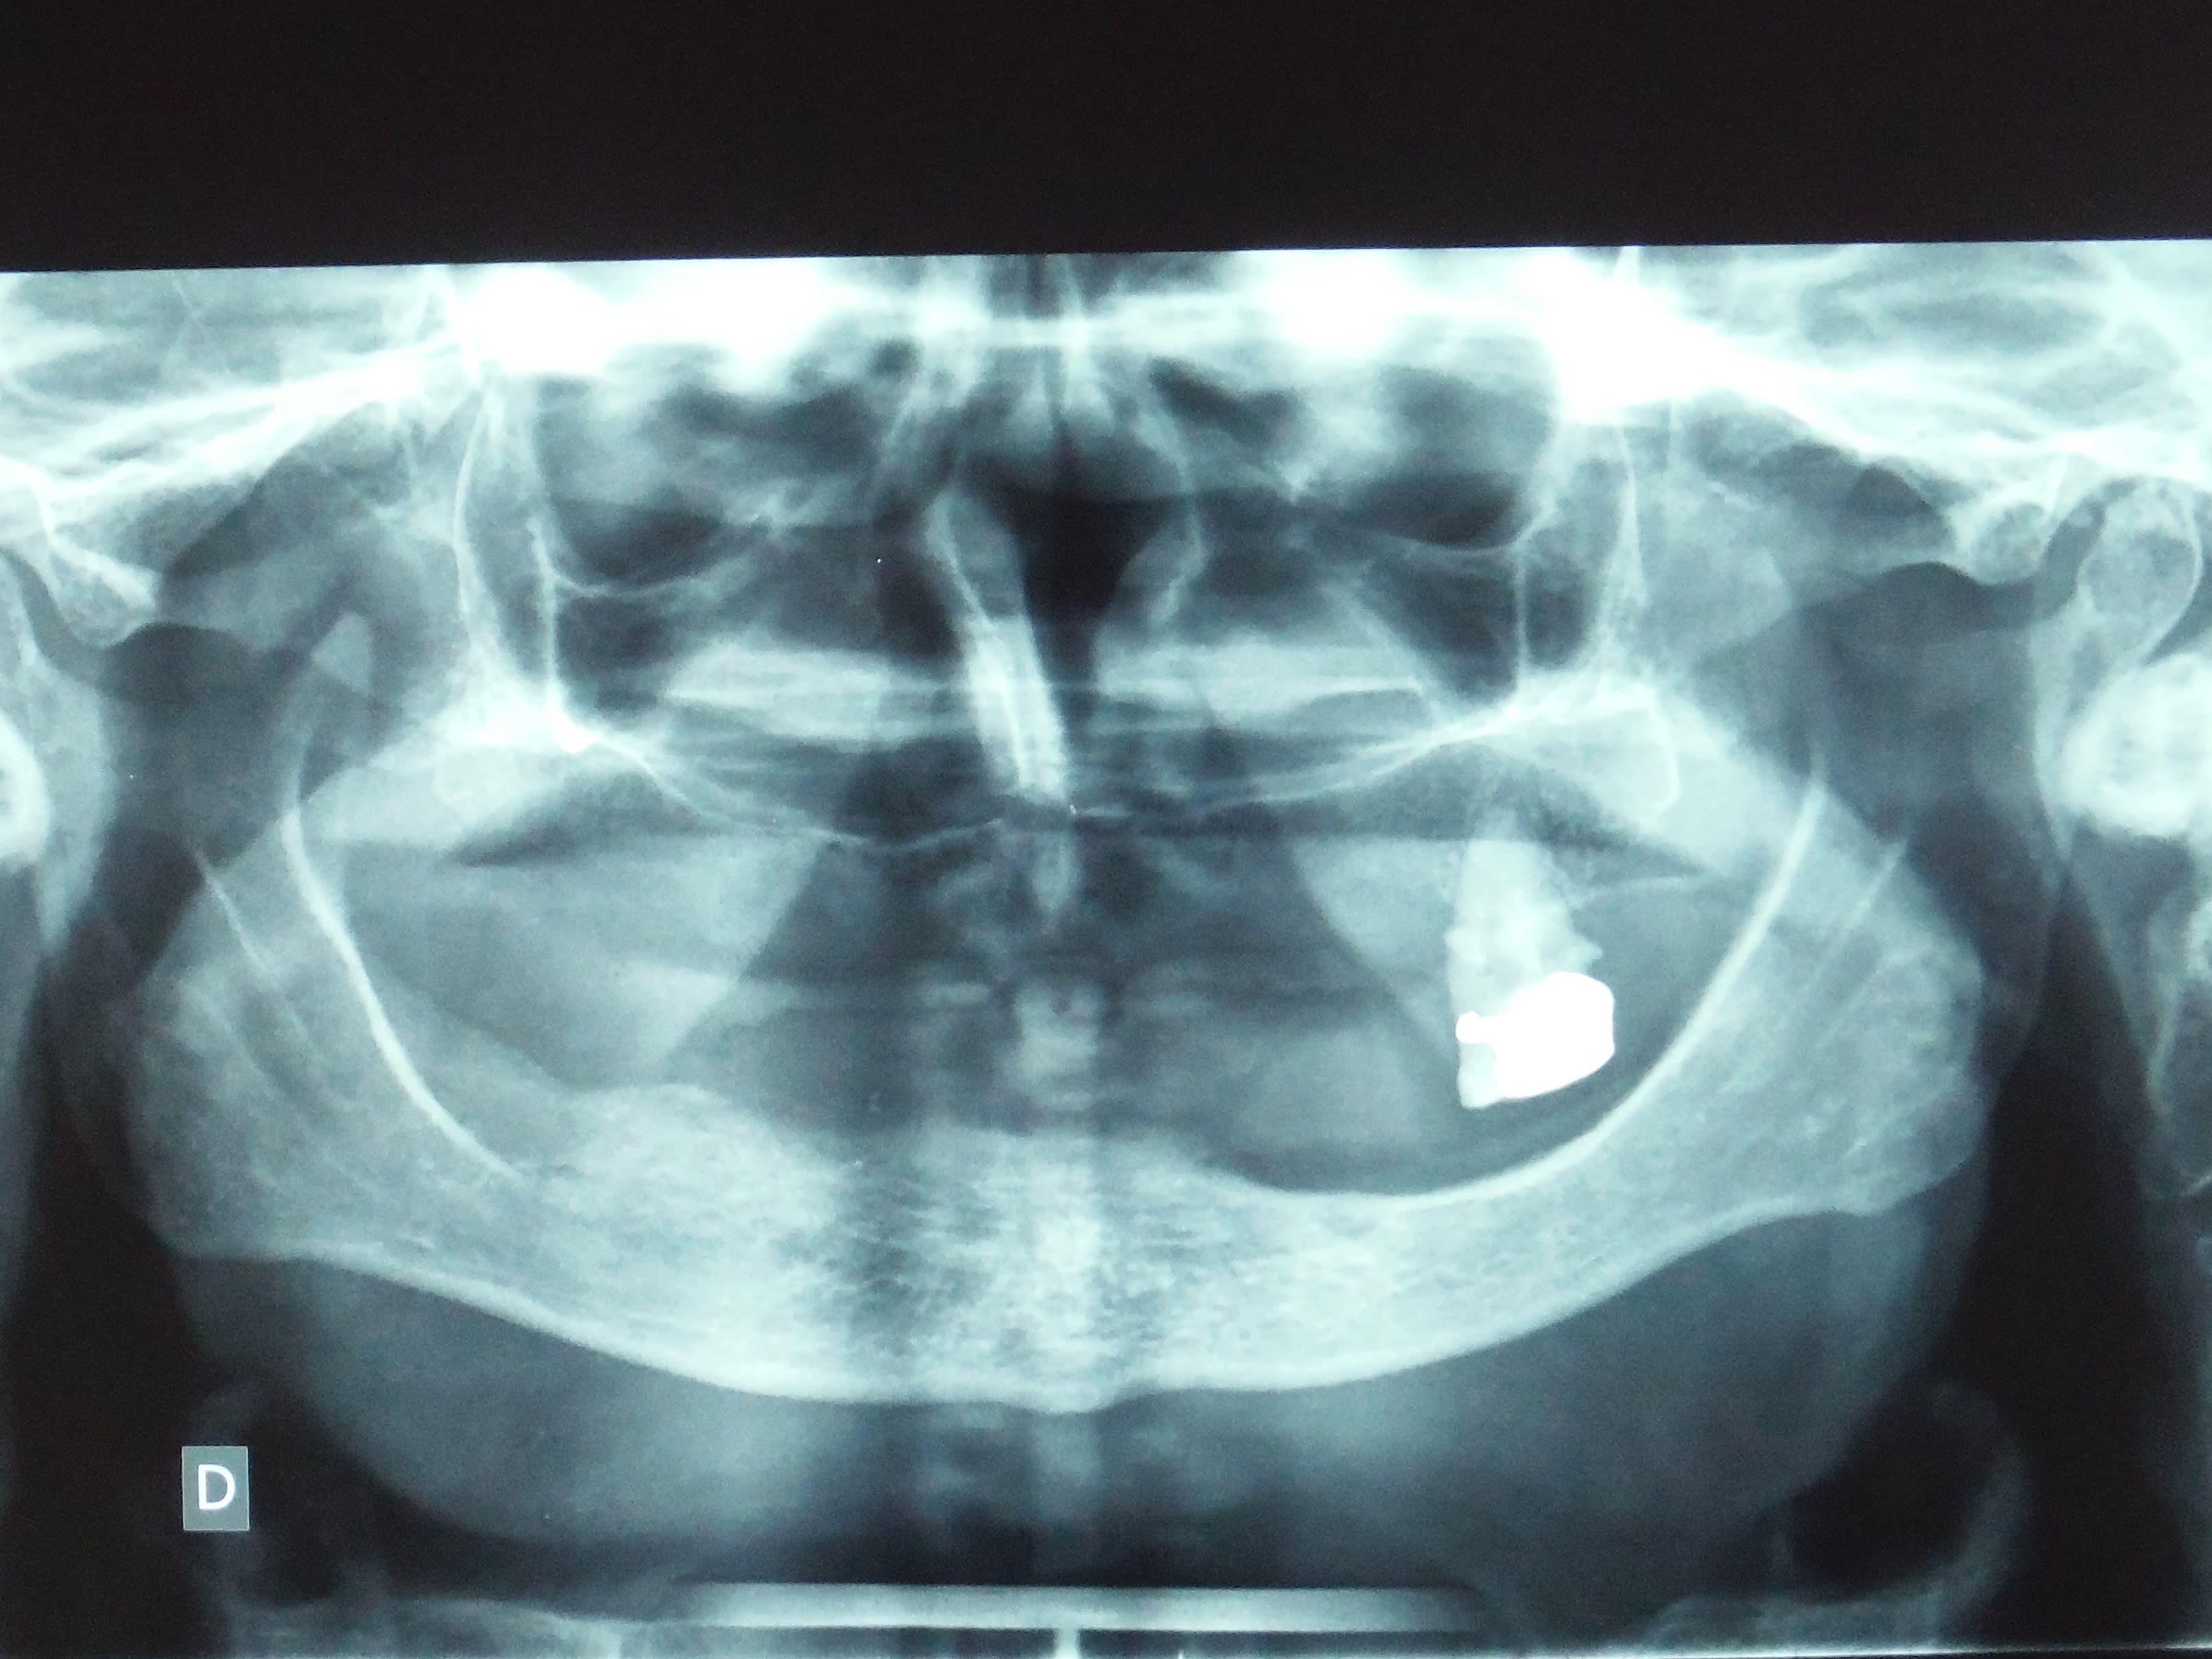

Le même mois j'ai eu ça, j'ose pas le dire, j'ai fait une corono sur la 26 (27?) et je l'ai conservé, la patiente y était attachée.

Pas de crête à la mand à gauche.

> pano ci-jointe

> patiente avec peu de moyens financiers.

A la mandibule, montage directeur,puis PAC immédiate avec remontée de DV+++

Au maxilaire exo 11-21 prothèse transitoire 3 dents, cicatrisation osseuse puis transitoire 5 dents, j'attends que les autres tombent.

En augmentant la DV + coronos mineures j'ai créé la place pour la pac mand aux niveau PM et M, pour les 3 reliquats incisives, une fois extraites, comme souvent, il y avait la place.

C'est un compromis bien sûr. J'ai revu la patiente en contrôle lundi, elle est satisfaite.